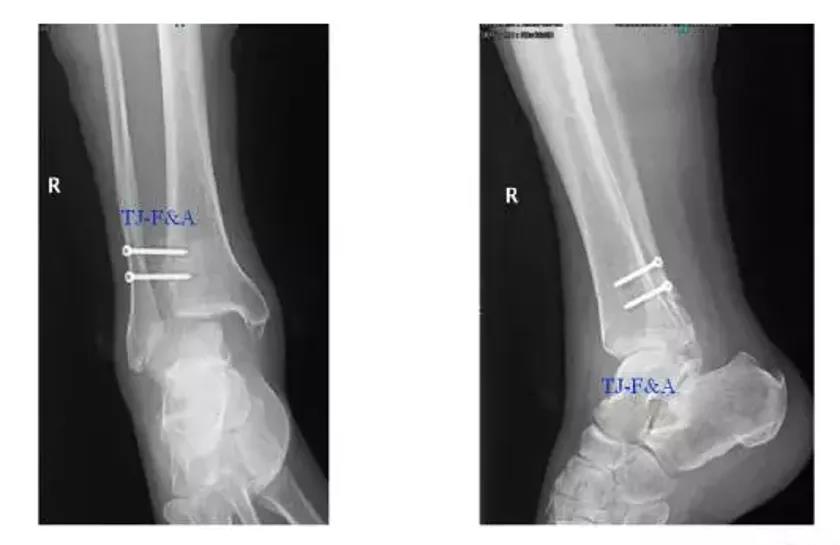

术后DR

术前DR